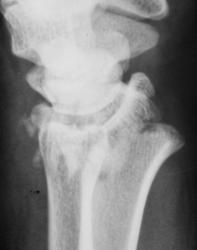

Маловато будет. Дополняю... Со смещением к тылу под углом и по ширине, плоскость эпифиза лучевой кости открыта к тылу под углом *** градусов (стояние отломков неудовлетворительное). Разрыв дистального луче-локтевого сустава.

Отвечаю как коллеге. ///Что есть что? Когда можно говорить о неудовлетворительном или наоборот?/// Точных данных под рукой нет, очень велика доля субъективизма. Общее правило: "Ну, не нравится мне это!!!". Все смещения по ширине просто отмечаю, в долях (1/4, 1/3, 1/2) от поперечника кости, Главное, стояние оси. Угловые смещения до 10 градусов считаются допустимыми. Плоскость эпифиза лучевой кости в норме открыта кпереди под углом 5-10 град. Горизонтальное положение можно считать допустмым. Небольшой наклон плоскости эпифиза кзади - можно считать относительно допустимым, но должен отмечаться в протоколе http://www.radiomed.ru/content/travma-pierielom-biez-smieshchieniia-kostnykh-otlomkov. Представленный случай ни в какие ворота не лезет: тут верные 25 град., более того предположительная ось кисти проецируется за пределы заднего края лучевой кости.

Хирург не ошибся, перелом классический, "луча в типичном месте", как любят писать травматологи. Да еще и внутрисуставной, оскольчатый.